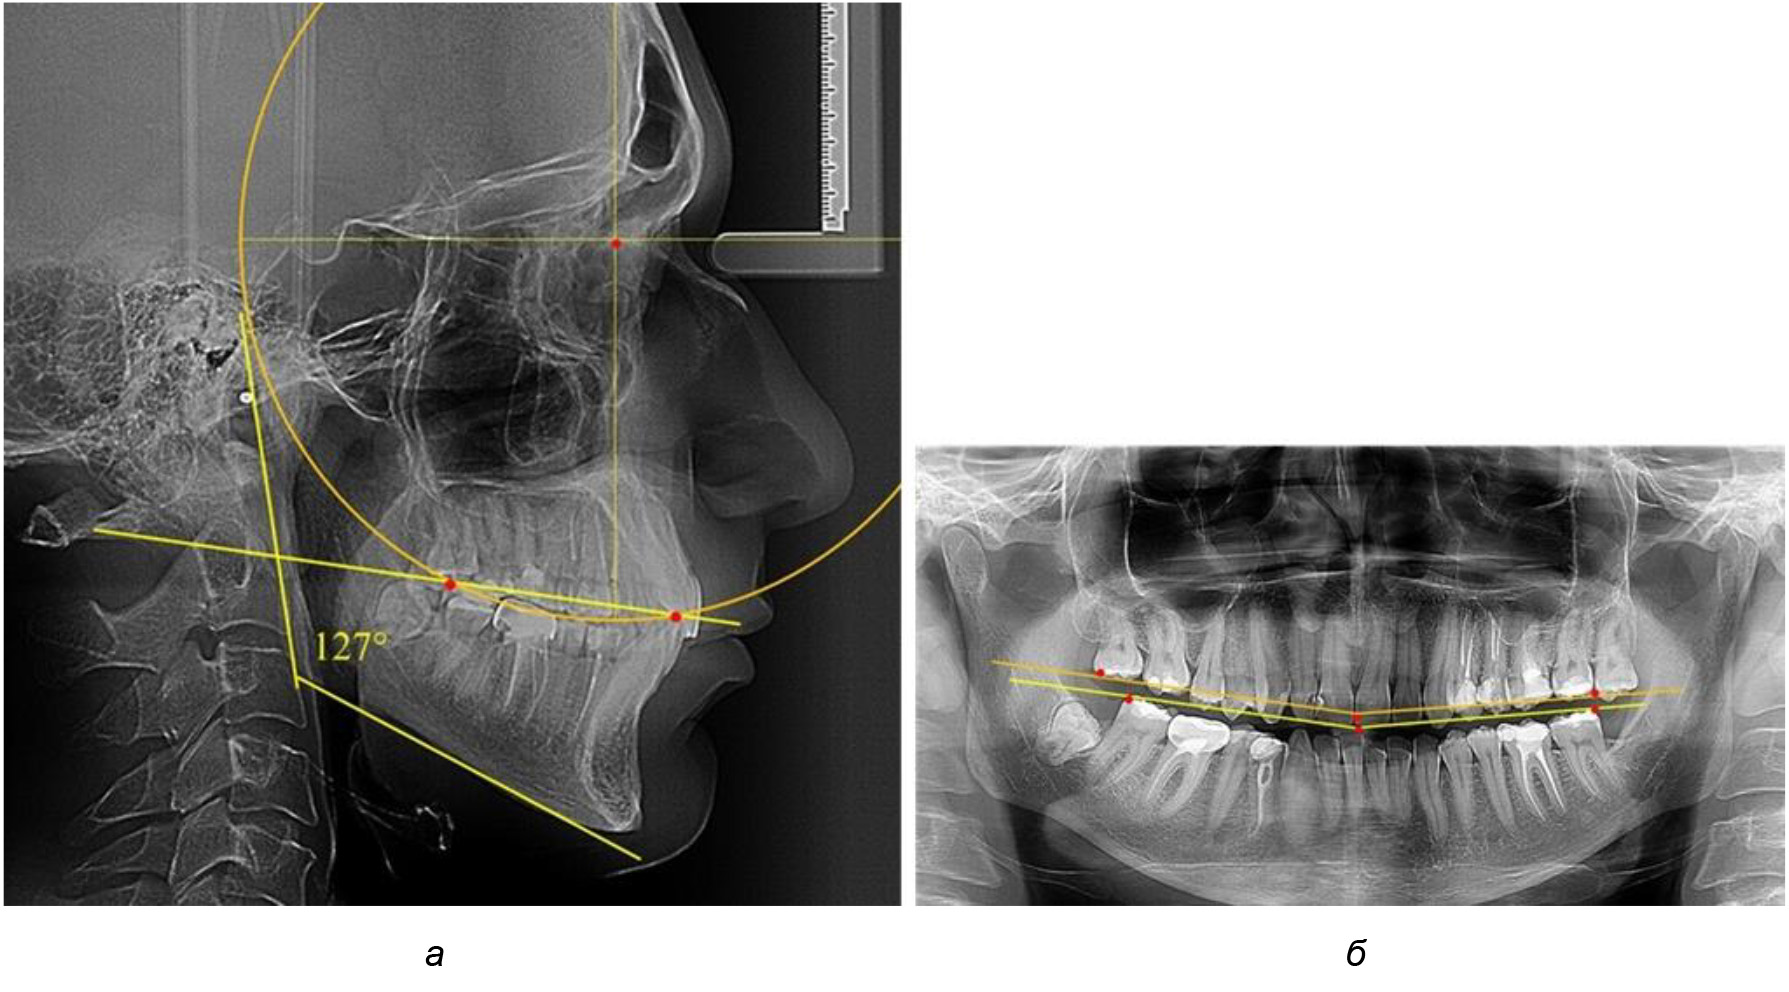

В ходе исследования установлено, что в 1-й подгруппу вошли ТРГ и ОПТГ 18 человек 1-й группы, что составило (29,03 ± 5,78) % от всех пациентов, рентгенограммы которых были проанализированы. У всех пациентов величина угла нижней челюсти была более 125° и в среднем составила (129,89 ± 3,62)° и характеризовала вертикальный тип нижней челюсти.

Анализ результатов показал, что глубина кривой Spee в среднем по подгруппе составил (4,12 ± 0,53) мм как при анализе ТРГ, так и ОПТГ.

Деление величины радиуса круга к длине окклюзионной линии составило 1,623 ± 0,02. Таким образом, для определения радиуса окружности, соответствующей кривизне окклюзионного контура боковой ТРГ, необходимо измерить расстояние между передней и задней окклюзионными точками и последующим умножением полученной величины на число Фибоначчи (рис. 2).

Рис. 2. Особенности кривой Spee на ТРГ (а) и ОПТГ (б) у людей с признаками вертикального роста